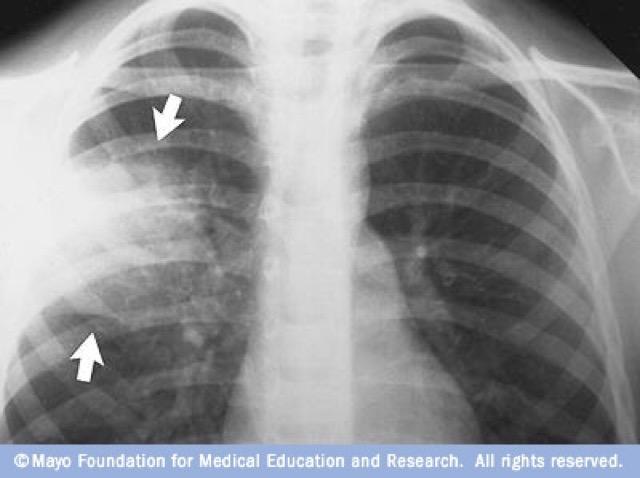

- Neumonía focal no segmentaria o lobar: afectación de un solo lóbulo del pulmón

- En la neumonía lobar, el exudado inflamatorio comienza en los espacios aéreos distales adyacentes a la pleura visceral y luego se propaga a través de rutas de deriva de aire colaterales (poros de Kohn) para producir una opacificación uniforme y homogénea de segmentos parciales o completos de pulmón y, ocasionalmente, de todo un pulmón. En ocasiones, la infección se manifiesta como un foco esférico de consolidación. Con frecuencia se observa un broncograma aéreo. S. pneumoniae es, con mucho, la causa más frecuente de consolidación lobular completa. Otros agentes causales que producen consolidación lobar completa incluyen K. pneumoniae y otros bacilos gramnegativos, L. pneumophila, H. influenzae y, en ocasiones, M. pneumoniae.